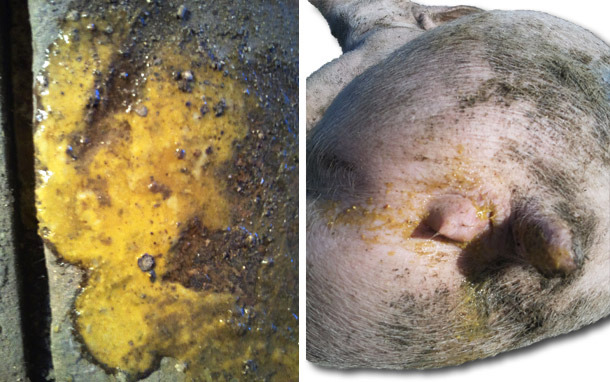

- Diarree giallastre con presenza di fibrina.

- Uno di questi con sangue coagulato nelle feci, presenta ittero.

. Nei suini con quadro acuto (necroscopia su un soggetto colpito e sacrificato con pentotal sodico).

- Lesioni macroscopiche.

- Ingrossamento della mucosa nella parte distale dell'intestino tenue (ileo terminale), che si presenta rigido e si osserva attraverso la sierosa.

- Ileite proliferativa nella zona prossima alla valvola ileo-cecale. Mucosa umida con pieghe e molto ingrossata.

- Presenza di frangie leggermente adese.

- Gangli linfatici mesenterici ingrossati.